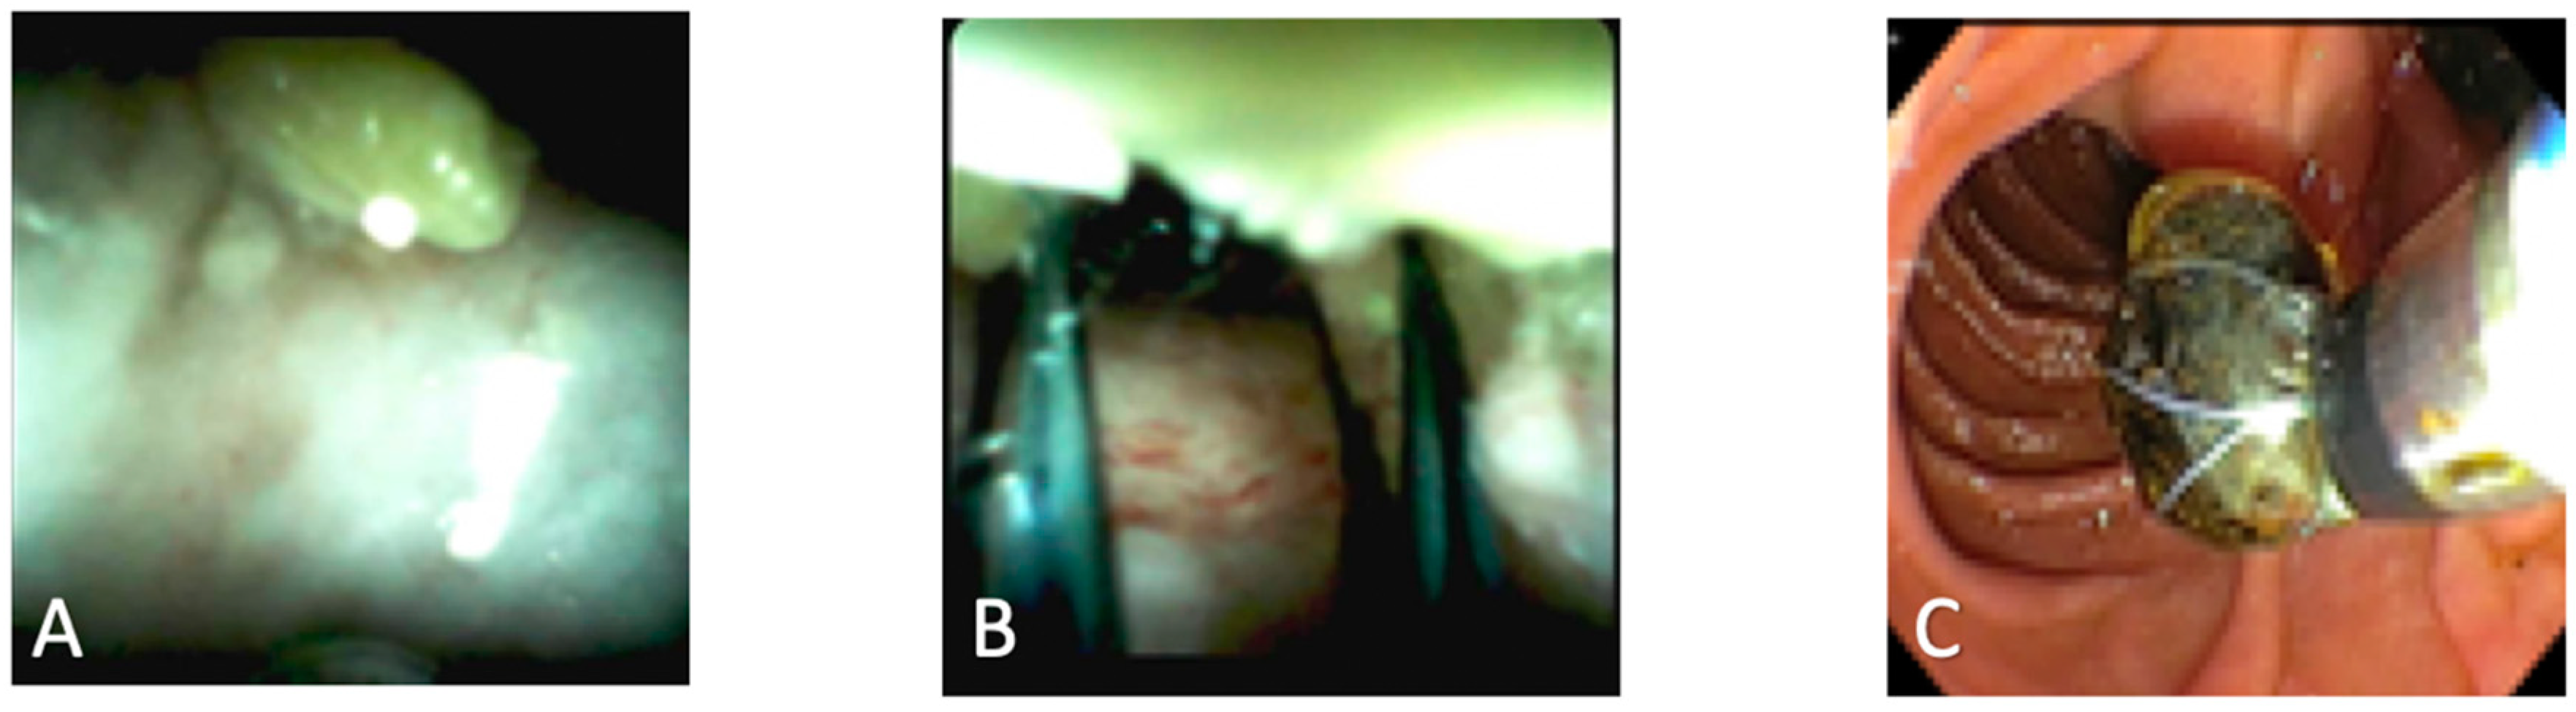

2. Biliary Stones

| Visually guided electrohydraulic and laser lithotripsy |